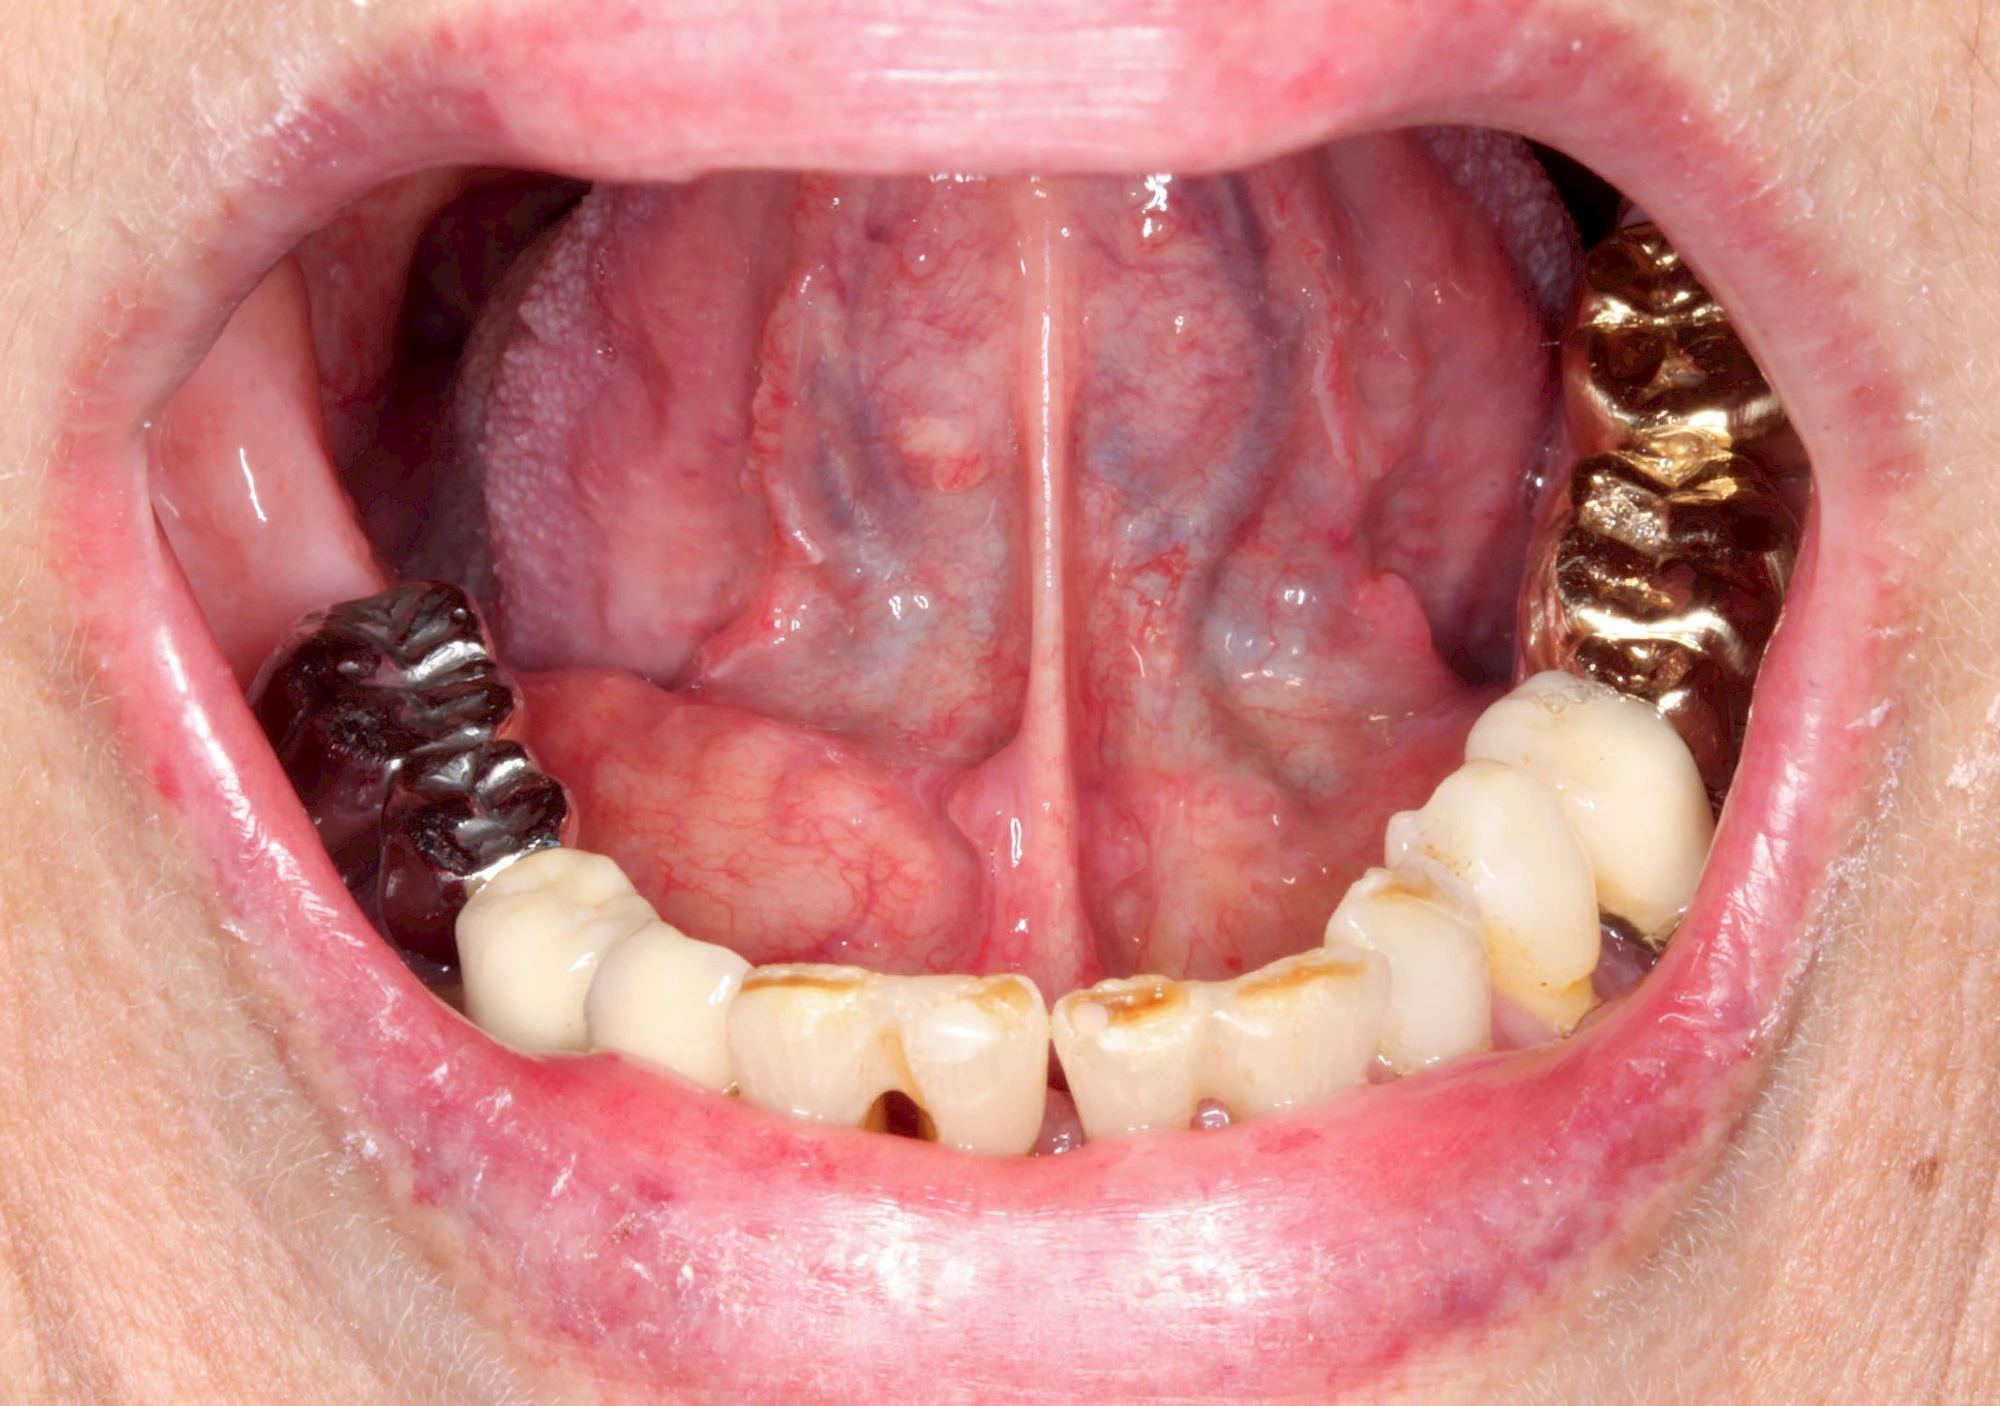

Mandelstein

Mandelsteine (Tonsillenstein oder auch Tonsillolith) sind Reste von Gewebe, Speisen, Entzündungszellen und Bakterien können vereinzelt im Bereich der Gaumenmandeln beobachtet werden. Ggf. sollten die aktuellen Mundpflegemaßnahmen überprüft und ggf. angepasst werden.